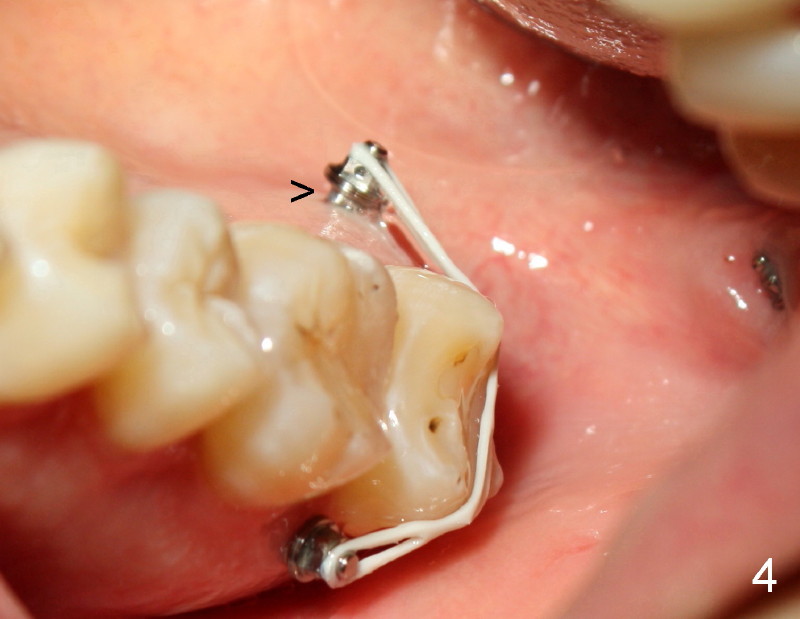

Small incision is made in the retromolar area. Pilot drill is used before a 10 mm Ancor Pro Mini-implant is placed (Orthoorganizer). But it is too loose. Incision is extended distally. With shallower pilot drilling, the next placement of mini is stable (Fig.2). With placement of lingual button on the mesial aspect of #31 and power chain (Fig.2,5), the journey of distalization begins. But it is not so easy as expected.

Mini penetration does create soft tissue shaving, which may cause epithelial entrapment and therefore potential mini loosening. At time of placement, it is a minor issue, in comparison to violation of root surface. As the mini goes down, torque builds up. Finally the handpiece halts. Then use a wrench to slowly rotate the mini down while watching for patient's reaction. It appears that the mini eventually has resistance (touching root surface?). The mini does not seat completely (Fig.4 >, as compared to Fig.3 <), but it is solid. When power chain is loaded, it is apparent that the patient feels more pressure upon #2. The patient tolerates the procedure with topical well. It feels like that champagne is needed for celebration. Sweeter is taking and looking at immediately post-op PA (Fig.7 >).

The good things about mini is that if mini does not catch the bone (stability), counter-rotate it, find a new spot and do it again until you hit home run (Fig.2). The wound heals uneventfully in spite of bloody field. Since the maxilla has spongy bone, pilot drilling is not required. The palatal root of the maxillary molar is narrower mesiodistally than buccal. Therefore, mini can be placed a little bit closer to the palatal root than buccal. The tip of mini is directed apically so that there is more room for placement.